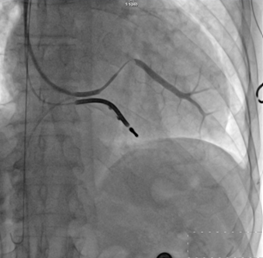

冠狀靜脈逆行造影

?“它的技術(shù)難點(diǎn)在于左室電極的植入”。朱彬介紹,除了常規(guī)的由于心臟擴(kuò)大變形所致的冠狀靜脈竇口位置改變,自身冠狀靜脈解剖異常等問題外,傳統(tǒng)的左室電極安置后存在起搏位點(diǎn)選擇性小,起搏時(shí)容易出現(xiàn)膈神經(jīng)或膈肌刺激、起搏高閾值、為保證穩(wěn)定性將電極植入心尖而出現(xiàn)心尖部起搏,為避免心尖部起搏避開心尖位置但卻出現(xiàn)電極不穩(wěn)定術(shù)后移位等諸多問題。而左室四極電極導(dǎo)線由于可以有多個(gè)起搏位點(diǎn)和多種起搏向量的選擇,可一次性解決上述難題,能做到“電極植入心尖,起搏心底”。綜合患者具體情況,為提高手術(shù)成功率,降低手術(shù)風(fēng)險(xiǎn),朱彬決定在該手術(shù)中使用目前國內(nèi)最新型的左室四極電極。